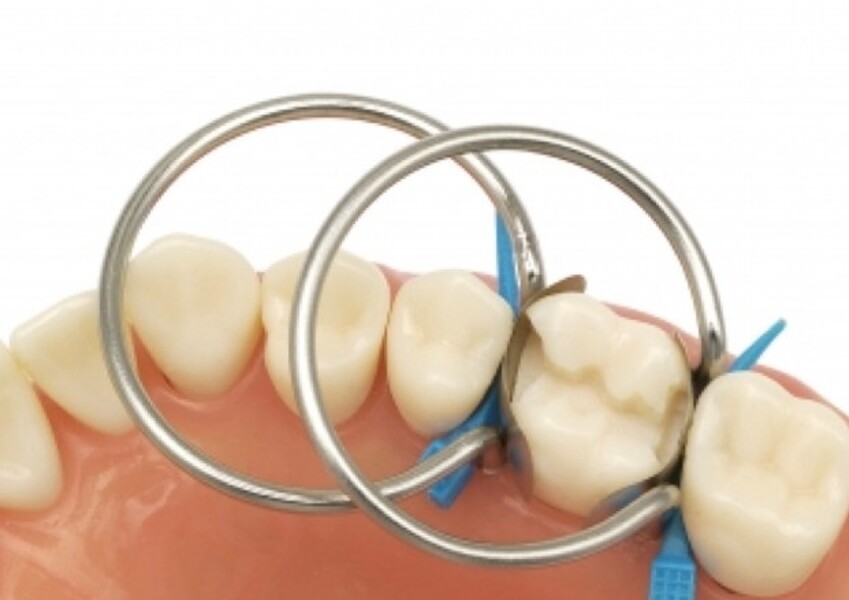

Predictable posterior restorations